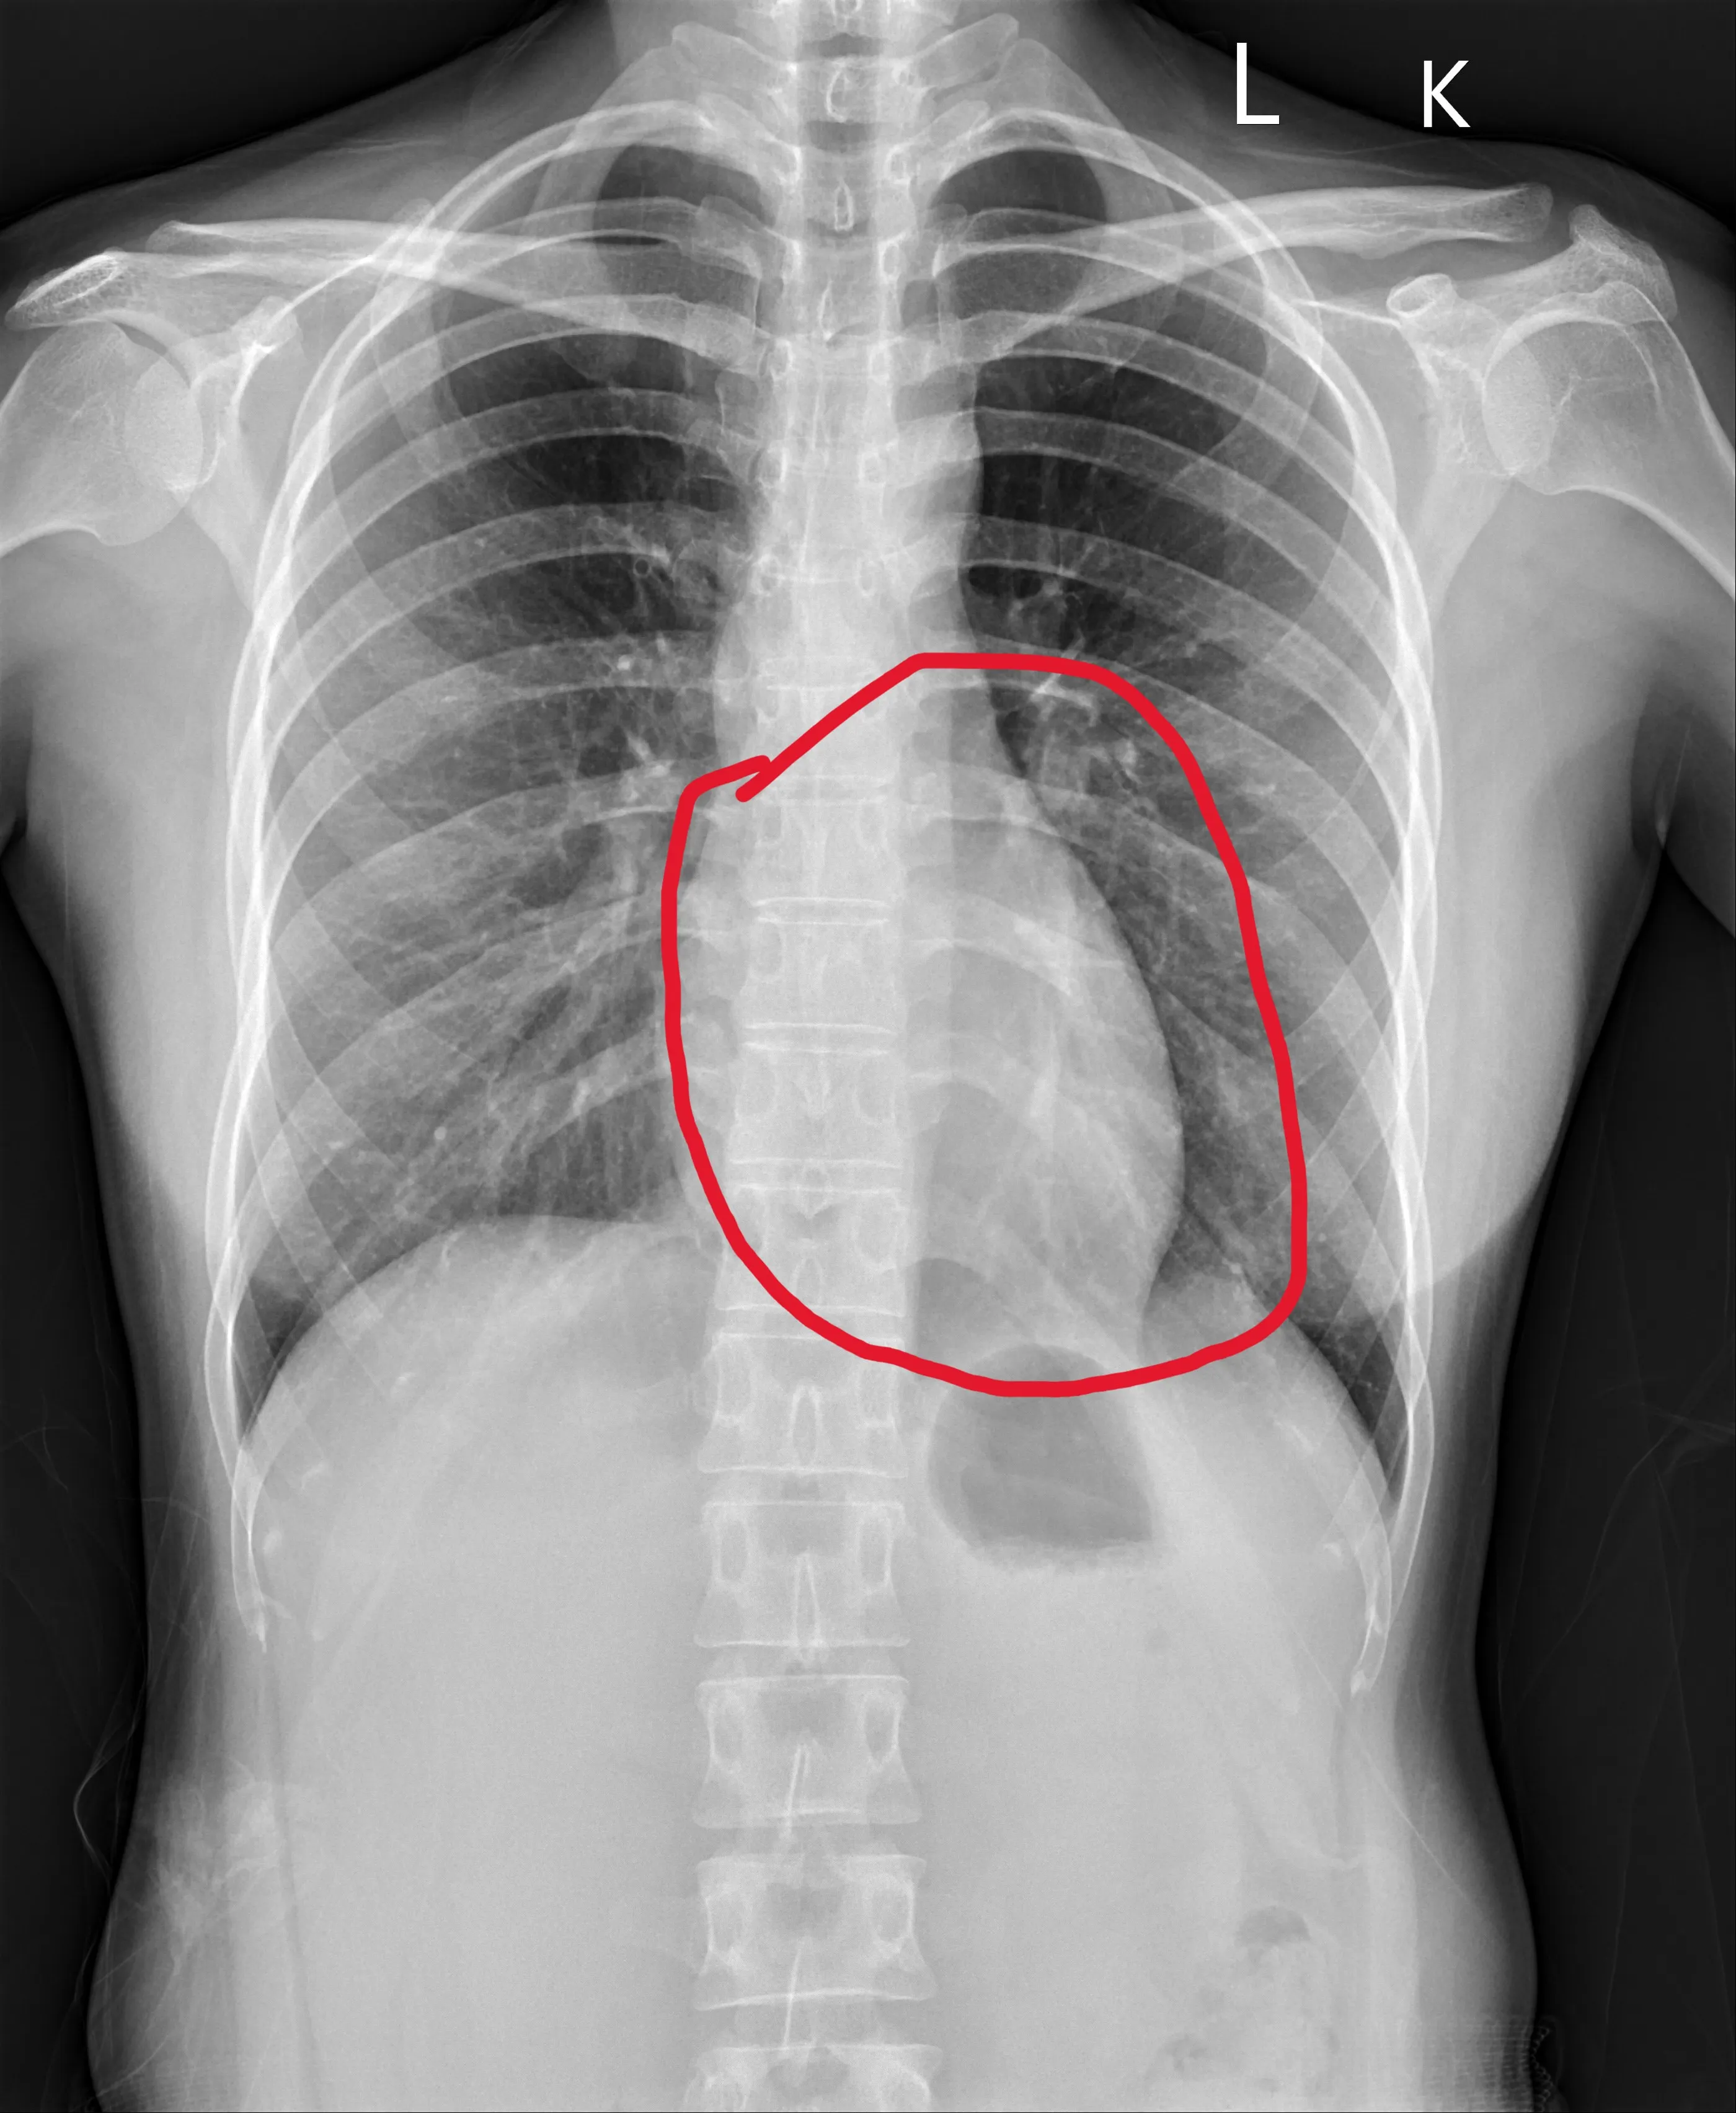

26歲患者今年6月的X光,顯示經過10個月的治療,其心臟(紅圈內)已明顯縮小。(員榮醫院提供)

員榮醫療體系員榮醫院心臟內科主治醫師陳裕峰表示,患者就醫時並沒有喘或胸悶等典型症狀,但心臟收縮功能非常差,左心室射出分率只有39%,一般應該至少要50%以上,甚至60%以上才算正常,39%已符合心臟衰竭,心臟超音波發現瓣膜逆流比較嚴重。之後為患者制定一系列心臟衰竭標準治療,經10個月治療,心臟大小已恢復正常,左心室射出分率從原本的39%大幅進步到59%,接近正常值。